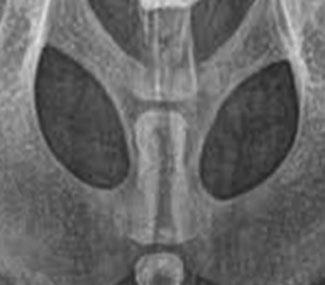

Issuu converts static files into: digital portfolios, online yearbooks, online catalogs, digital photo albums and more. Sign up and create your flipbook.